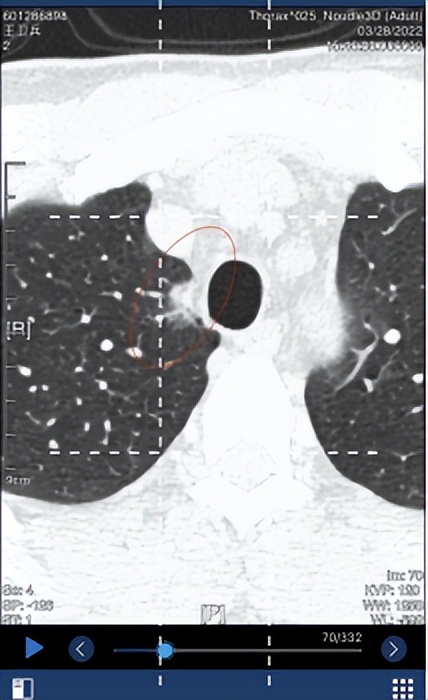

3. 2022.1.26日复查,SE4/7IMG70右肺上叶尖段见一混合密度影,病灶形态类圆形,边界不清晰,无分叶,有毛刺,有胸膜牵拉,无血管束集征,无空泡征。病灶前后径 12.6 mm,左右径 8.8 mm,上下径 18.7 mm。病灶平扫时密度为 -88HU。左肺下叶后基底段(SE4/7,IM205)见一枚磨玻璃结节,内见空泡影,长径约6mm。 右肺中叶及左肺上叶舌段少许斑片索条影。 两肺门区未见异常密度影。 胸膜未见增厚改变。 纵隔内未见异常密度影。